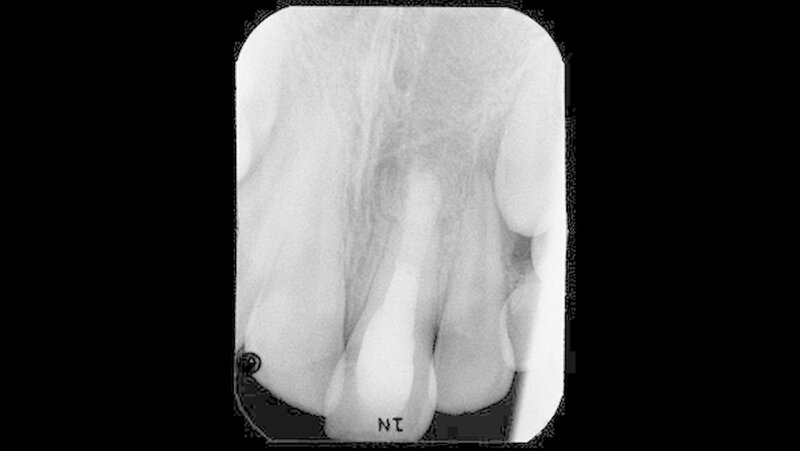

Das nach 22 Monaten angefertigte Röntgenbild (Abbildung 4) zeigt eine nahezu vollständige Regeneration der bei Behandlungsübernahme bestehenden apikalen Osteolyse. Trabekelstrukturen im vorherigen Lumen lassen eine Ausheilung des Knochendefekts vermuten. Ein Längen- beziehungsweise Dickenwachstum der Wurzel lässt sich nicht erkennen. Ob durch weitere Einlagen von Kalziumhydroxid ein vollständiger apikaler Verschluss erreicht werden kann, erschien nach der bislang schon langen Behandlungszeit fraglich.

Die Aufnahme ist 25 Monate nach Behandlungsübernahme angefertigt worden. Im Vergleich zur Voraufnahme ließ sich eine weitere Ausheilungstendenz und Zunahme der Radioopazität im Bereich der vorherigen apikalen Osteolyse erkennen.